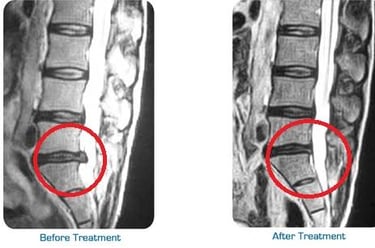

With advanced Chiropractic Adjustment techniques and Varmam Manipulation balancing techniques most of the spine related issues L4 L5 S1 disc buldge, Scoliosis, sciatica, Leg pain, knee Pain, lower Back pain, neck and Shoulder pain can be resolved with ease without Surgery avoiding further complication.